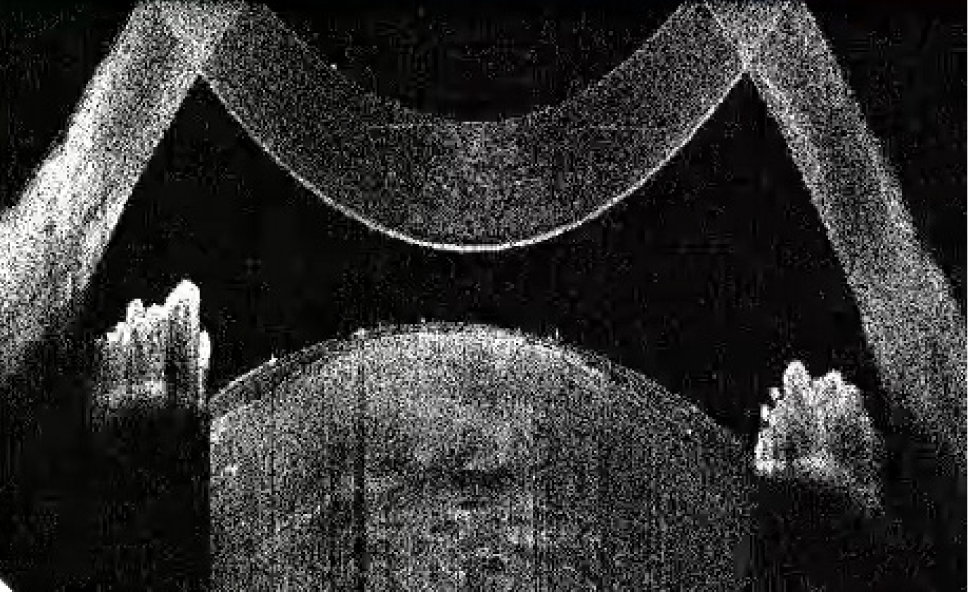

В исследование вошли 196 пациентов (250 глаз) с перезрелой катарактой. Пациенты были разделены на 2 группы (по 125 глаз в каждой группе). Всем пациентам интраоперационно с помощью интегрированной в операционный микроскоп И-ОКТ, Hi-R NEO (HAAG STREIT, Германия), определяли тип перезрелой катаракты (рис. 1–4).

Рис. 2. Тип 2 перезрелой катаракты: непрерывные гиперрефлективные полосы кортикальных волокон, множественные внутрихрусталиковые щели, оводнение хрусталика